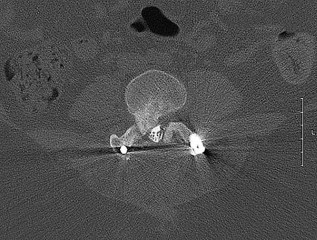

A 72-year-old woman with chronic pseudoparalysis of the shoulder undergoes the procedure shown in the radiograph below. Which of the following is the most commonly reported radiographic complication specifically associated with this biomechanical implant design?

Explanation

The image depicts a reverse total shoulder arthroplasty (RTSA). Scapular notching, caused by mechanical impingement of the medial humeral metaphysis against the inferior scapular neck during adduction, is the most common radiographic complication. It is historically highest with medialized glenosphere and inlay humerus implant designs.